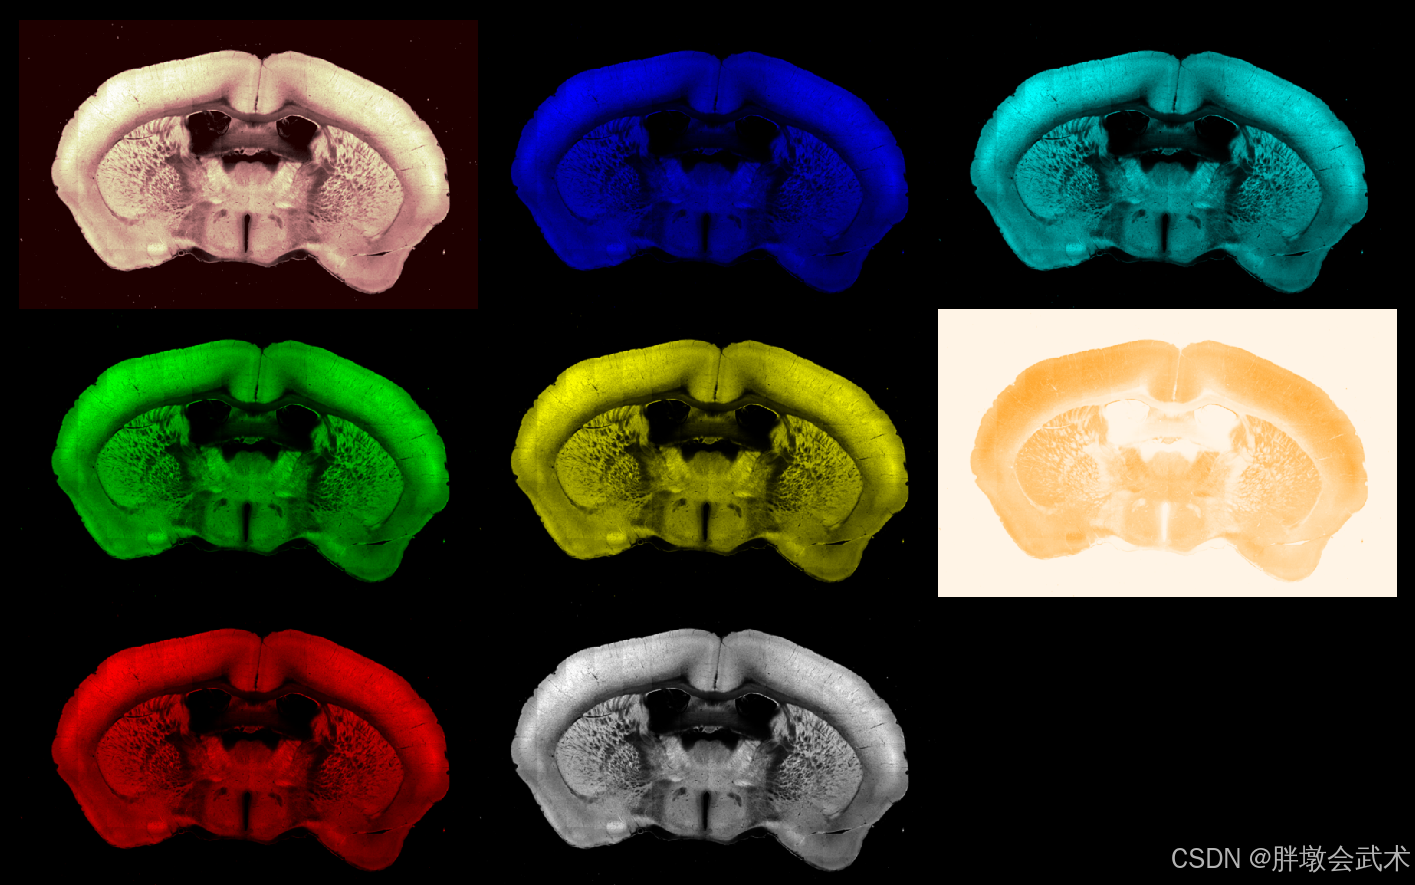

3.2.3、(自动)启动网格视图模式(Toggle grid mode)

import napari

import tifffile

if __name__ == '__main__':

image_path = r'F:\py\YH220.tif'

image = tifffile.imread(image_path)

viewer = napari.Viewer() # 创建 napari 视图

viewer.add_image(image, name='image1')

viewer.add_image(image, name='image2', colormap='red') # 红

viewer.add_image(image, name='image3', colormap='orange') # 橙

viewer.add_image(image, name='image4', colormap='yellow') # 黄

viewer.add_image(image, name='image5', colormap='green') # 绿

viewer.add_image(image, name='image6', colormap='cyan') # 青

viewer.add_image(image, name='image7', colormap='blue') # 蓝

viewer.add_image(image, name='image8', colormap='pink') # 粉(不支持紫色)

viewer.grid.enabled = True # 启动网格视图模式

viewer.grid.shape = (3, 3) # 设置网格的行和列数

napari.run() # 显示 napari 视图